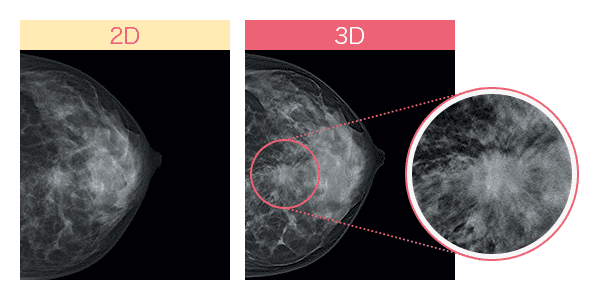

さらに進んだ「3Dマンモグラフィ(トモシンセシス)」とは?

従来のマンモグラフィ画像は、平面の撮影(2D)のため乳腺と病変が重なると、判別が難しく正確な診断に時間を要することがあります。

しかし最近では乳房内の構造をより正確に描出できる「3Dマンモグラフィ(トモシンセシス)」が登場して、より高い精度で乳がん検査を行うことが可能になりました。異なる角度から乳房の画像を複数撮影し、それを再構成して乳房の断層像を生成することで、乳腺の重なりが除外でき、これまで発見が難しかった病変の観察がしやすくなりました。*4